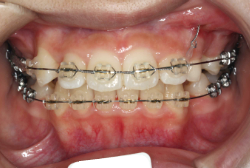

牽引(埋伏犬歯を牽引した症例)

埋伏歯とは、骨または歯茎の下に埋まって出てこない状態の歯のことを言います。埋伏歯があると歯が押されて歯並びが悪くなってしまったり、永久歯が生えてこれない原因になる恐れがあります。

「乳歯が生え替わらない」という主訴で来院したケースです。 診断の結果、「左上永久犬歯が第一小臼歯後方上部に埋伏しているため、左上乳犬歯が晩期残存している症例」と判明しました。

このような症状の場合は、手術で埋伏している永久歯に金具を取り付け、矯正装置で牽引する必要があります。同時に凸凹の解消と前突した前歯を内側に入れるために上下左右の小臼歯を抜歯させて頂くことといたしました。

この方の場合は、マルチブラケット装置にて治療を開始し、治療期間2年3ヶ月で終了しました。犬歯の牽引距離が非常に大きかったため当院の平均治療期間よりも大幅に期間がかかりましたが、埋伏犬歯を完全に正しい位置まで誘導することができました。同時に 前歯の前突と配列の凸凹も解消しました。

このような症例は、成人してしまうと埋伏歯の反応性が悪く、あまりにも動きが悪い場合は牽引をあきらめて抜歯する場合もあります。歯科医院の検診で親知らず以外の埋伏歯を指摘された場合は、できるだけ早く矯正専門医に御相談下さい。